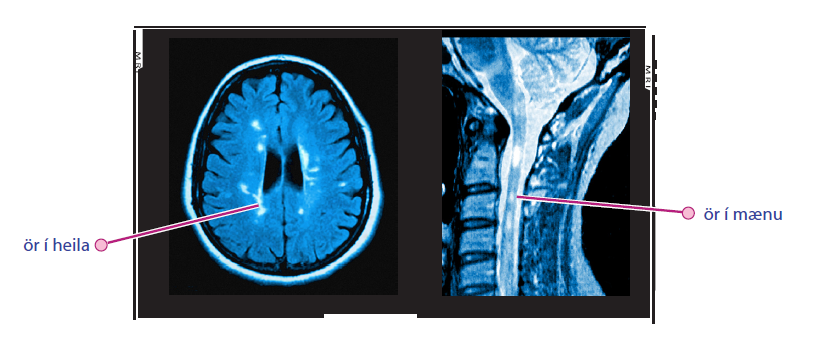

Við dæmigerðan MS sjást segulskærar eða hvítar skellur (MS-ör/MS-skemmdir/ e. plaques) í heila og stundum í mænu á segulómunarmyndum. Slíkar breytingar eru ekki alltaf sértækar fyrir MS en ákveðið mynstur af þeim ásamt einkennum er notað til greiningar.